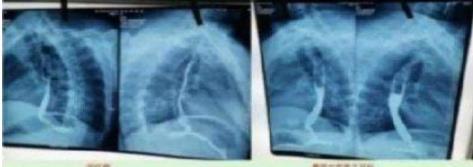

这是治疗前:病变长约 7 ㎝。从吃饭困难到滴水不 进。

2023 年 10 月 9 日在山西肿瘤检查:病变长度 7 ㎝。从 2023 年 10 月 28 月开始服用中药;2024 年 3 月 24 日拿中药:2024 年 8 月 29 日山西肿瘤医院 复查(病变 7cm 癌变消失)。 目前:吃饭一大碗,一切很好,参加农业劳动。这是一 位贫困山村的农妇。

食道癌患者从吃饭困难到滴水不进。经两次治 疗:7 公分的食道癌经省肿瘤医院 CT 检查:病灶消 失。至今每顿一大碗,馍头,面条。米饭都能,并时 常参加农业劳动!两个月临床治愈! 患者送上锦旗以表对陈海林医生的感谢 案例 3.、近日,陈海林教授中医治疗成功挽救重症患者的消 息引起了广泛关注。据悉,该患者陈香花在经历了西 医的多次手术、化疗和放疗之后,身体状况急剧恶化, 最终被多家医院拒之门外。在生命即将走到尽头的时 候,被好心人送到陈海林中医诊所。更严重的是该患 者有多种严重疾病缠身,包括失去右肺、左肺功能仅 剩三分之二,并伴有心脏病、贫血、高血压等十多种 基础疾病,生命垂危。面对这样一位多种病且复杂的 危重患者,陈海林教授秉承救命优先的原则接诊了这 位患者,经过仔细的辨证施治,陈教授为患者制定了一 套个性化的中医治疗方案,在经过长达七个月的纯中 医治疗后,患者竟奇迹般地恢复了健康,重新获得了新 生,也创造了中医药治疗重症肺癌的奇迹。

上图是服用两个月中药的前后对比图

上图是服用两个月中药后检查报告对比图 食道癌的显效率为 100,五年存活率 90%,20 年以 上存活率 40%。中间断层的分别意外事故,医院一过度医治。心梗,脑出血,自然老去的。没有复发,转变,十 七位患者至今 10 位生存着。 案例 8、食管中段乳头状瘤的治疗 一位长者 86 岁高龄,在 33 年前生食道(乳头状瘤), 在文献中记载:必须己癌对待,恶变很高。当时患者怕 做手术才来找我想用吃中药的方法,把病治好。当时 我根据他的请求结合影像学和病理检查报告,进行细 致地分析研究,各种药的性能,炮制,主治,对症组方进行 服药,每用一付药总要详细观察:服药量的多少,服下去 的感受?是否有恶心,呕吐,头晕,心慌,意乱,失眠,大小是 否正常,等等,直到上述症状都没有时我才放心,大胆地 为他治病,经过四至五个的的纯中药治疗,患者的病证 完全消失了,吞咽功能恢复正常。经山西大学临床二 院病检,一般炎症。一次性治疗至今 33 年未见复发, 未见转移,不服药,安享晚年幸福时光。四十五种癌症, 癌细胞逆转正常生理细胞就是吴老这里开始的!